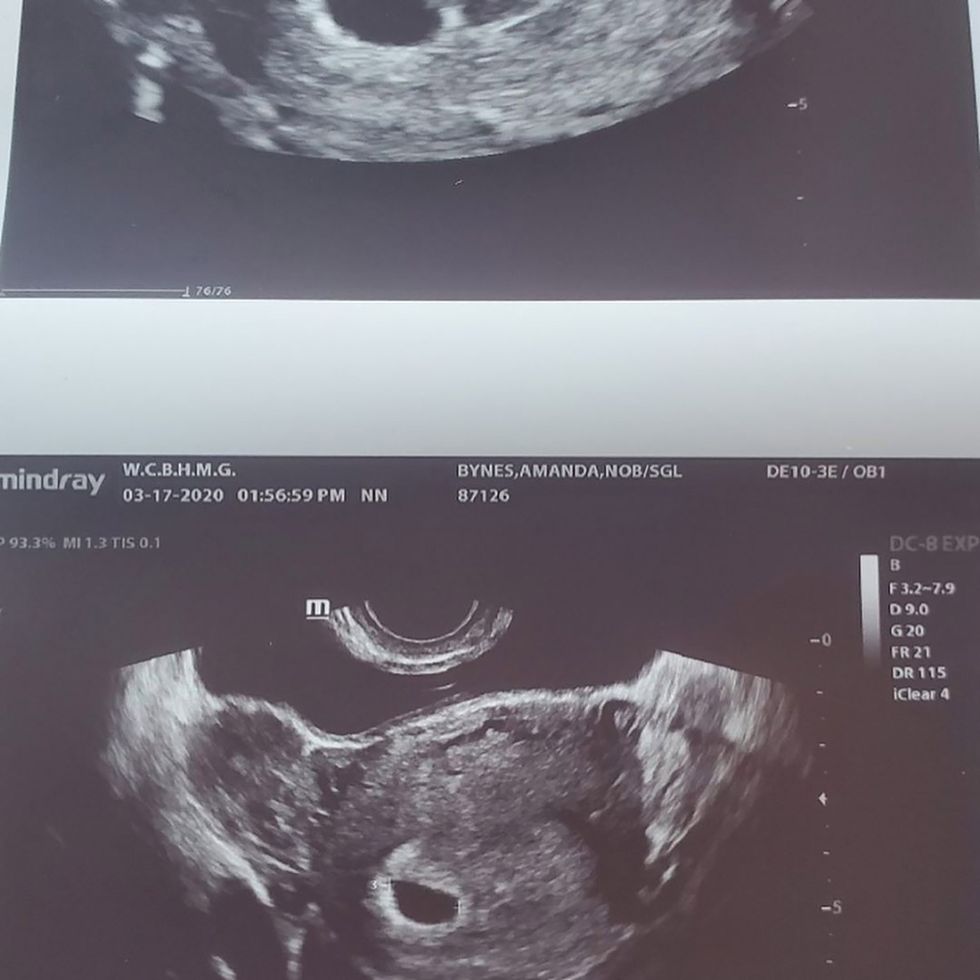

Të martën, Michael ndau një postim në rrjetin social, Instagram, ku përfshin një selfie të vetes dhe yllit të "She's Man", si dhe një foto me ultratinguj me emrin Bynes në të.

"Foshnja në bërje", e përshkroi Michael postimin e tij.